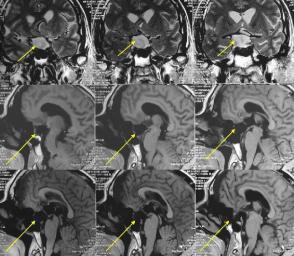

王先生,60岁,近半年来出现视物模糊,一直未被重视,直到头痛接近昏迷才检查,被发现鞍区巨大垂体瘤,此时手术创伤大,而且风险极高。

如果早期发现,可以接受创伤小的经鼻部手术切除,该患者因肿瘤巨大,只能颅骨打开手术,手术风险很大。

幸运的是这位患者顺利的度过了手术等难关,目前恢复良好。

术后一月患者尿量稍多,不需要服用防止尿崩药物,口服强的松及优甲乐替代治疗,复查血电解质正常,甲状腺功能检查基本正常。